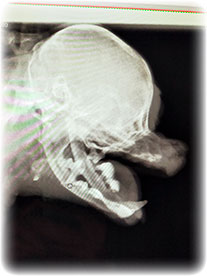

レントゲン撮ったら

まさかの下顎骨骨折という大変な事態(泣)。

特にどこか強くぶつけた感じはなかったけど

昔からの歯槽膿漏で骨が溶かされ

薄皮1枚状態で

いつこうなってもおかしくなかったらしい。